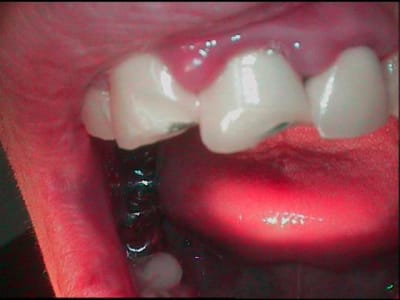

porte poisse va!!! m'en arrive un beau,accident de vtt, de plus les anterieures sont solidarisées entre elles, le gamin n'a pas un rond, il etait pas assuré,et les muqueuses saignent des qu'on les regarde, et il est malheureux comme les pierres...et bien sur....il n'a pas de dentiste...

gamin avec des CCM sur les antérieures ?

ET des molaires bien blindees

pfff...23 ans...bin oui quoi gamin!!!! qui fait le fou en vtt casquette en arriere, pas assuré, sans job, chez papa et maman, qui veut plaire aux boutonneuses et qu'est pas en bonne passe...

le verrai lundi soir en quinze, ferai des photos du visage, verrez bien...gamin gamin gamin!!!

oui bin plus tard!!! veux bien rendre service mais faut aussi que je survive dans ce monde brutal, alors photo pour montrer que c'est un gamin quand meme...

le 22 mai,reception d'une photo d'un gamin

*est ce la photo de ton patient?

*dans ce cas,pourquoi ce rendez vous précipité?

*l'as tu convoqué pour prendre la photo pour satisfaire notre curiosité?

*si c'est lui,comment se fait il que tu n'aies pu

simple, me suis gourré, c'etait aujourd'hui, pas la semaine prochaine, j'étais le premier étonné de le voir fleurir aujourd'hui